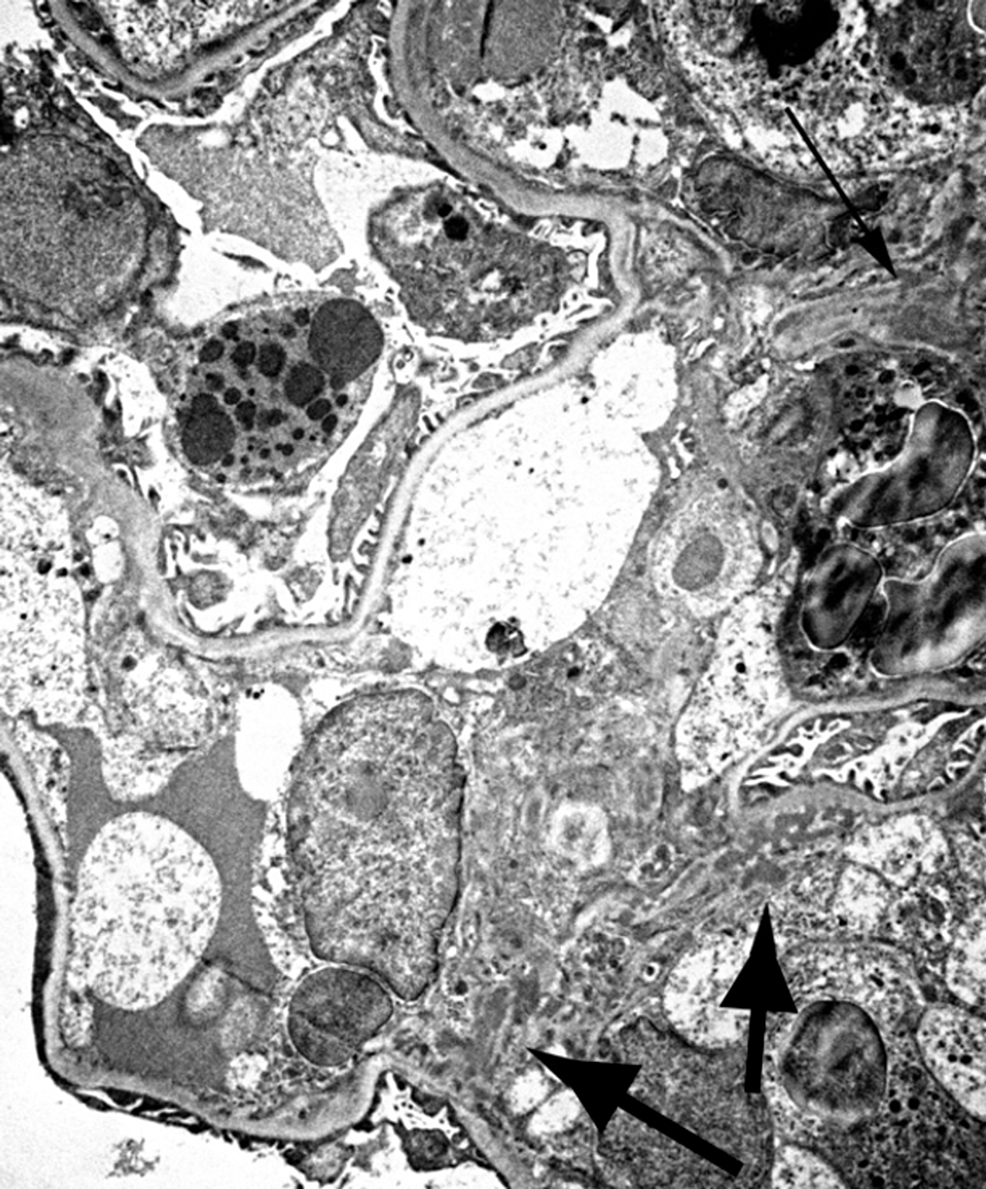

Figure 5. [Electron microscopy in subacute poststreptococcal Post Streptococcal Glomerulonephritis Electron Microscopy Postinfectious glomerulonephritis (gn) presents as acute nephritic syndrome with low complement c3 in serum, commonly following streptococcal throat or skin infection. On electron microscopy, has characteristic hump type large subepithelial deposits, occasional mesangial deposits and rare. Poststreptococcal glomerulonephritis (psgn) is an acute glomerular inflammation that follows infection with nephritogenic strains of. Post Streptococcal Glomerulonephritis Electron Microscopy.

Post Streptococcal Glomerulonephritis Electron Microscopy . Postinfectious glomerulonephritis (gn) presents as acute nephritic syndrome with low complement c3 in serum, commonly following streptococcal throat or skin infection. On electron microscopy, has characteristic hump type large subepithelial deposits, occasional mesangial deposits and rare. Poststreptococcal glomerulonephritis (psgn) is an acute glomerular inflammation that follows infection with nephritogenic strains of.